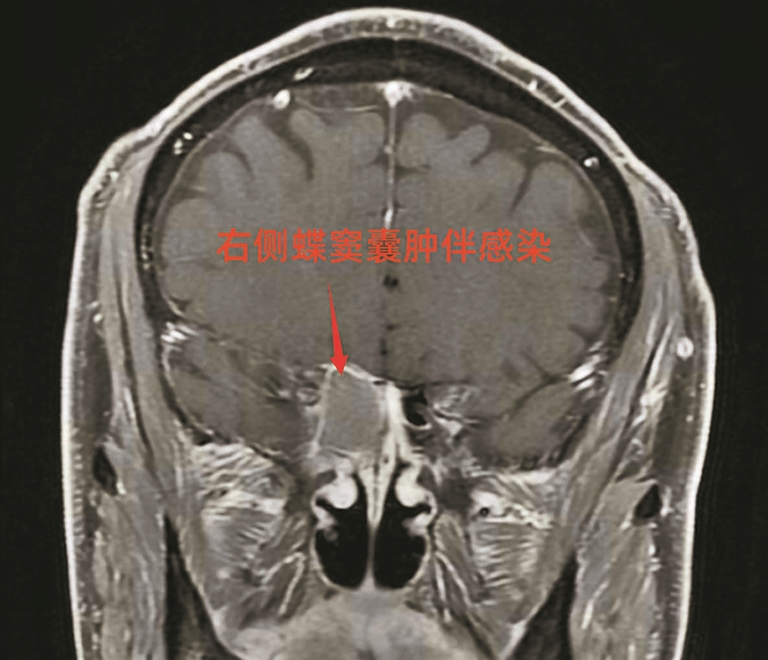

老田核磁检查发现蝶窦囊肿。

住院后,杨成明立即为老田安排了头颅核磁共振、颈动脉彩超等关键检查。次日结果提示:蝶窦内有一个30mm×20mm的囊肿。蝶窦位于鼻腔深处、颅底位置,紧邻视神经。

经耳鼻喉科进一步检查,确认右侧蝶窦囊肿严重压迫视神经,这正是其视力骤降的主要原因。